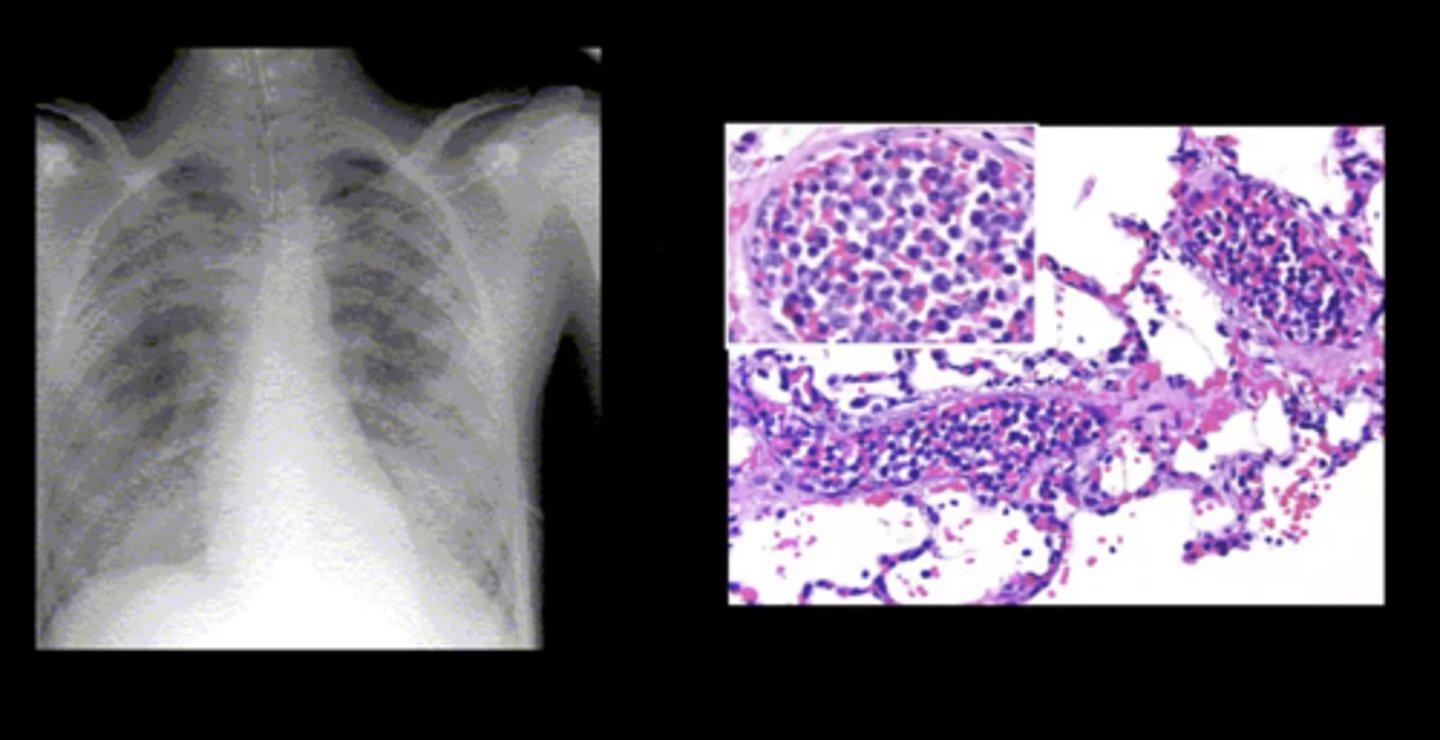

Pulmonary leukostasis

Sudden shortness of breath and progressive dyspnea; caused by a WBC clot

Leukostasis

Complication of acute leukemia; a severely elevated circulating immature WBC count --> blood is more viscous --> clot development